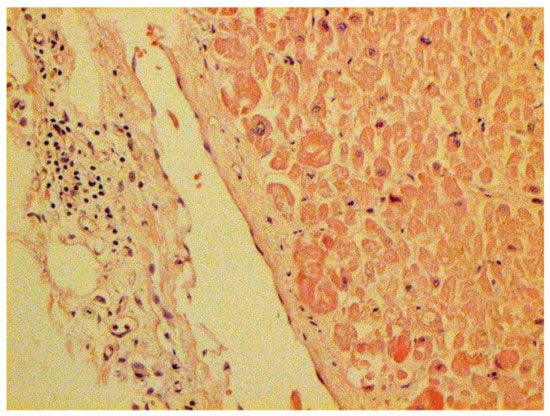

The dynamics of changes in ARDS associated with COVID-19 can only be judged by analogy with SARS and influenza A/H1N1pdm. In the late (productive) stage (after 7–8 days or more from the onset of the disease) of diffuse alveolar damage, macroscopically the lungs are enlarged, low-air, dense, fleshy, and can resemble the density of the liver, sometimes with diffuse whitish layers and areas of different sizes. Microscopically, siderophages, a relatively (in comparison with swine influenza) small number of hyaline membranes (Figure 9), fibrin, squamous metaplasia of the bronchial, and bronchiolar and alveolar epithelium can be detected in the lumens of the alveoli, respiratory and terminal bronchioles, the thickening of the interalveolar septa due to sclerosis, lymphoid (mostly CD3+ and CD 8+) (Figure 10 and Figure 11) and macrophage (Figure 12) infiltration, and the proliferation of type II alveolocytes. The nature of cytoproliferative changes of the epithelium in the trachea and bronchi remains unclear. In the final stage of the disease, sections of fibrous tissue may develop in all parts of the lungs (usually in the lower lobes) (Figure 13), which contributes to the development of chronic respiratory failure. It is notable that near the overgrowth of collagen fibers in the lungs, neoangiogenesis is also typical (Figure 14). The electron microscopic study revealed changed viral particles (Figure 15).

Figure 13. Fibrosis in lung due to collagen 3. IHC ×200.